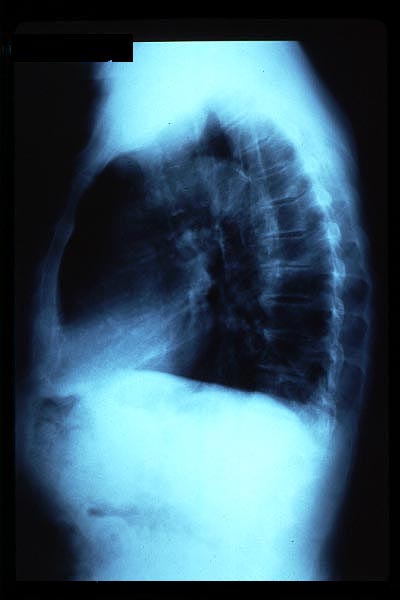

Osteoporosis. Cifosis.